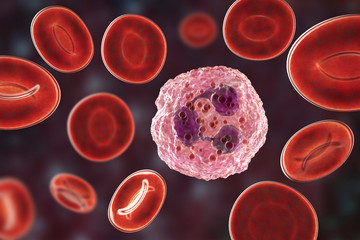

New Generation of Sensors Infectious Diseases Detection

Proteins for Serological Test of COVID-19

Antimicrobial Peptides for Antibiotic Resistant Germs